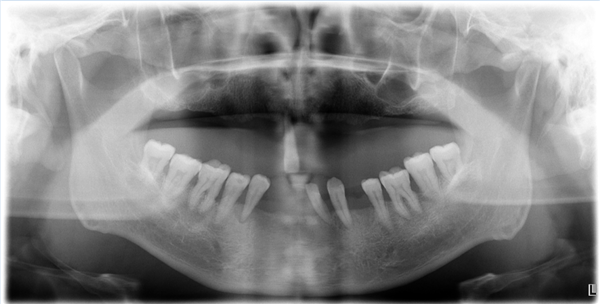

接诊的该科主任韩素勤,给陈先生做了全面口腔检查,结果让人揪心:

· 患有重度牙周炎,全口多颗牙不同程度松动,牙龈萎缩,红肿,探易出血。上颌仅剩1颗牙,但已经严重松动,无保留价值;下颌缺了5颗,还有三颗牙明显松动,移位,牙槽骨吸收;

· 更麻烦的是,由于牙周病一直未做治疗,导致牙龈萎缩,牙槽骨吸收,剩余牙槽骨骨量严重不足,上颌磨牙(大牙)缺牙区骨高度最低处不足3mm,距离上颌窦较近。